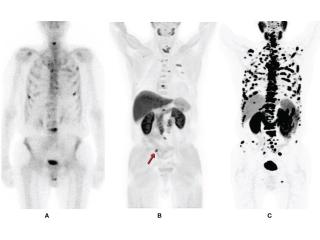

For men managing prostate cancer — whether newly diagnosed, post-treatment, or facing a rising PSA with no visible lesion on conventional imaging — a PSMA PET CT scan is now the most sensitive and clinically validated imaging tool available. Using Gallium-68 labeled PSMA tracer, this scan binds specifically to prostate-specific membrane antigen on cancer cells, lighting up even microscopic metastatic deposits that standard CT or bone scans routinely miss. Recent global trials confirm PSMA PET CT allows nearly half of men to avoid unnecessary biopsies entirely. Picture This in Mumbai generates its own 68Ga-labeled PSMA molecules in-house using a dedicated Gallium generator — a capability that sets them apart from most centres. Expert reporting is provided by Dr. Bhavin Jankharia and Dr. Nusrat Shaikh, with same-day results available for morning studies. Whether you need initial staging, biochemical recurrence evaluation, or treatment response monitoring, this is where precision prostate cancer imaging happens in Mumbai. Don't let uncertainty stall your care — contact Picture This now and get the diagnostic clarity your oncologist needs.